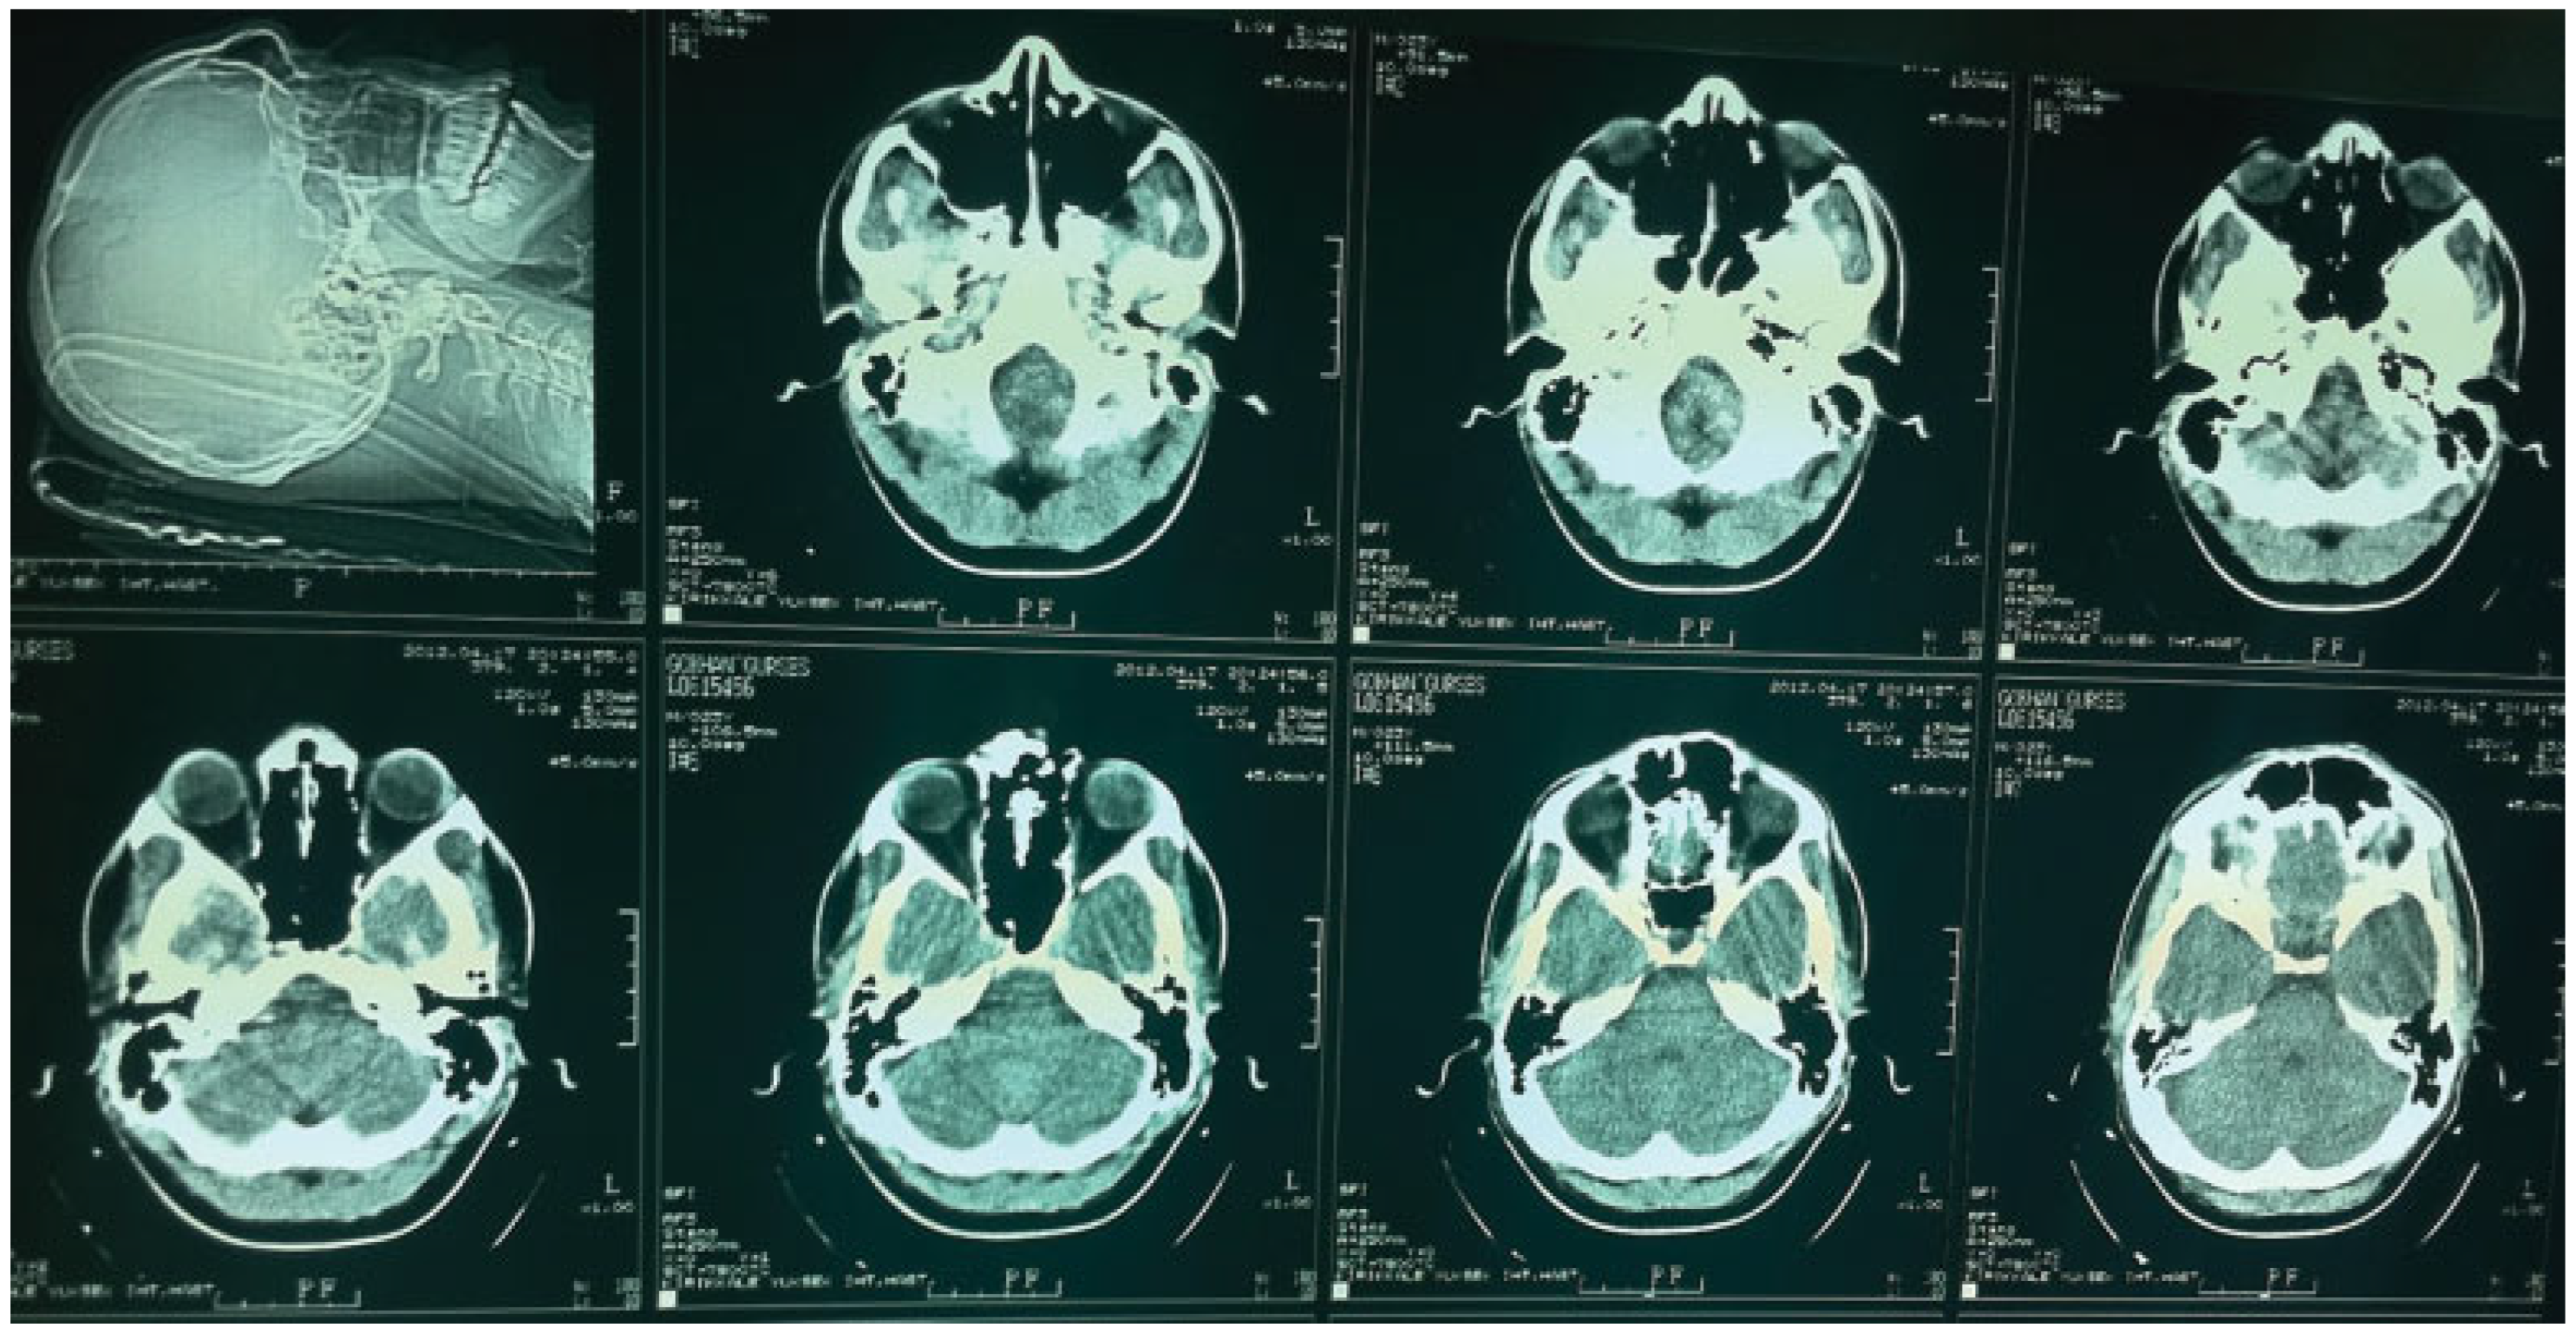

Case Report